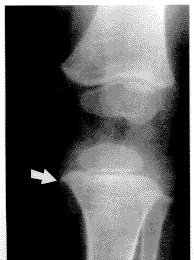

特异性骨骼改变 包括2种改变。一种是骨干条纹状改变,12例,于8个月~9岁之间均见此改变,其中>1岁者8例。X线片示高密度细条索影与骨干相平行,位于骨松质骨内,可延续延伸至干骺端(图1,2)。此12例中10例均伴有轻、中度脱钙。骨干条纹状改变均见于尺桡骨和股骨的长管状骨;二是干骺端两侧缘鸟嘴状突起,21例,见于股骨下端和胫骨上端大干骺端(图3)。本文37例患儿的各个年龄段都可以出现此种改变。

图 3 苯丙酮尿症女陔2岁4个月,示干骺端两侧缘鸟嘴

状突 起,以胫骨近端干骺端内侧为明

显。于胫骨、股骨干骺端可见横行的

生长障碍线。骨年齿测量相当6个月

-8个月婴儿